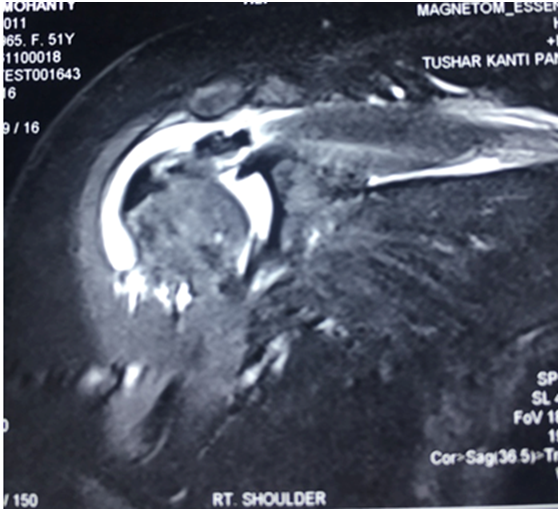

Figure 1 Preoperative radiographs (anteroposterior view) showing calcific deposits in the upper and anterior portion of the humerus.

A 50yr/Female with left upper limb monoplegia presented in outpatient department with complaints of pain in the right shoulder, with restricted movement of the right shoulder thereby affecting her activities of daily living, pain was sudden in onset present since last 3 months but was never shown to any physician since the intensity of pain was tolerable. On examination, the left upper limb had a power of Gr 0, Right shoulder there was wasting of the scapular and deltoid muscles. Tenderness was present on the right sterno clavicular joint, with flexion of 30 degree, abduction 20 degree and extension 10 degree. Drop arm sign positive, positive impingement sign, Test for subscapularis musculo tendinous belly press and lift off test was not possible. Blood test did reveal an uncontrolled Type II diabetes and echo showed a compromised cardiac status. Plain radiography showed a calcific deposit on the anterior and upper part of the humerus (Figure 1). Magnetic resonance imaging showed evidence of a calcific lesion in the supraspinatous tendon with evidence of partial tear of the rotator cuff (Figure 2). On the basis of these finding we made a diagnosis of calcific tendinitis of the supraspinatous tendon. The removal of the calcific tendon was challenging considering the disability of the patient, uncontrolled diabetes.

Figure 2 Magnetic resonance imaging showed evidence of a calcific lesion in the supraspinatous tendon with evidence of partial tear of the rotator cuff.